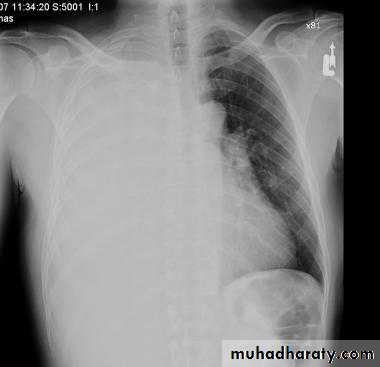

Pleural effusionX-ray of pleural effusion

Massive right effusion